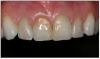

Figure 14 – Maxillary Anterior View

Figure 14